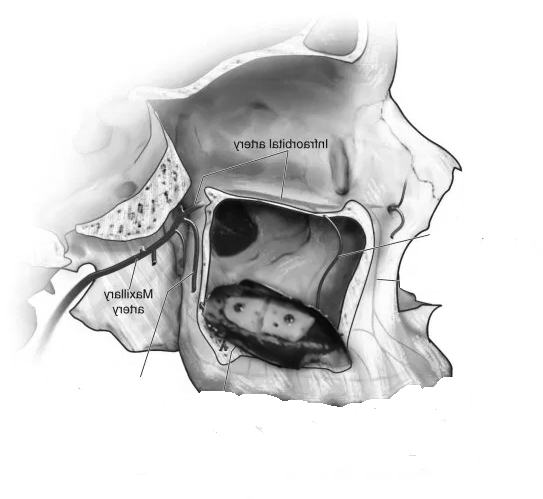

- Sinus Lift (Maxillary Sinus Elevation):

- At our center, we avoid this procedure thanks to Galileus Cerclage Sinus® surgery. In cases where the bone in the upper jaw is insufficient, a sinus lift procedure can be performed. This involves lifting the sinus membrane and adding bone graft material beneath it to improve bone density in the posterior maxilla.

- Zygomatic Implants:

- At our center, we avoid this procedure thanks to Galileus Cerclage Sinus® surgery. If not possible, we also avoid it with the Pterygoid Zygomatic technique. Zygomatic implants are longer implants anchored to the zygomatic bone (cheekbone). They are used when the maxillary bone is severely atrophied, providing an alternative to bone grafts or sinus lift procedures.